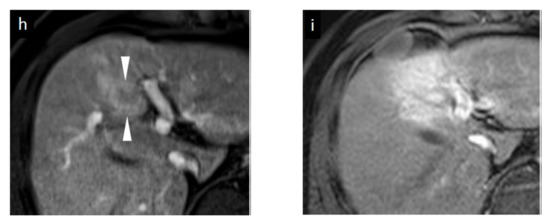

Figure 2.

Grayscale ultrasound (US), contrast-enhanced US with Sonazoid (SCEUS), and contrast-enhanced MRI (CEMRI) images before and seven months after radiotherapy (RT) for a HCC lesion (maximum diameter: 22 mm) in segment IV, evaluated as no local recurrence after RT. A safe punctuation was difficult, as the lesion was located behind the gallbladder. The patient refused surgical resection, so they received RT. SCEUS before RT (a–c): A hypoechoic lesion was observed using grayscale US (a). This lesion showed hypervascularity during the arterial phase (AP) of SCEUS (b) and hypoechoic (perfusion defect) during the post vascular phase (PVP) (c). SCEUS seven months after RT (d–g): Grayscale US showed a hypoechoic nodule and a reduction in tumor size (d). AP SCEUS showed a disappearance of vascularity of the HCC lesion and hypervascularity of the surrounding liver parenchyma (e). Both the HCC lesion and the surrounding liver parenchyma appeared as a perfusion defect during the PVP (f). After re-injection of Sonazoid during the PVP, the HCC showed hypovascularity and the surrounding liver parenchyma showed hypervascularity (g). AP CEMRI before (h) and seven months (i) after RT: Before RT, this lesion showed hyperintensity during AP CEMRI (h). Both the HCC lesion and the surrounding liver parenchyma appeared as hyperintensity at seven months after RT (i). Seven months after RT, we observed a discrepancy between the vascularity shown by SCEUS and that by CEMRI, but the lesion has not recurred for more than 3 years, suggesting that the SCEUS findings might be correct. Arrowheads show the margins of the HCC lesion. Arrows show the margins of irradiated surrounding liver parenchyma.